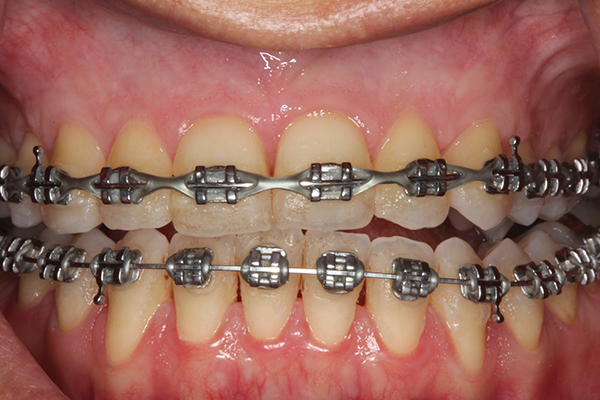

Fig 2. Full-thickness flap reflection. Note

dehiscence and fenestrations throughout. Orthodontic walls are limited to nonexistent.

Figure 2

Fig 3. Corticotomy cuts performed.

Figure 3